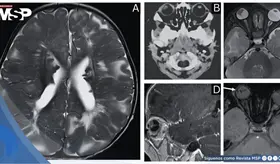

La ruptura de una aguja espinal durante una cesárea urgente dejó un fragmento de 4 cm en la musculatura paravertebral de una paciente embarazada.